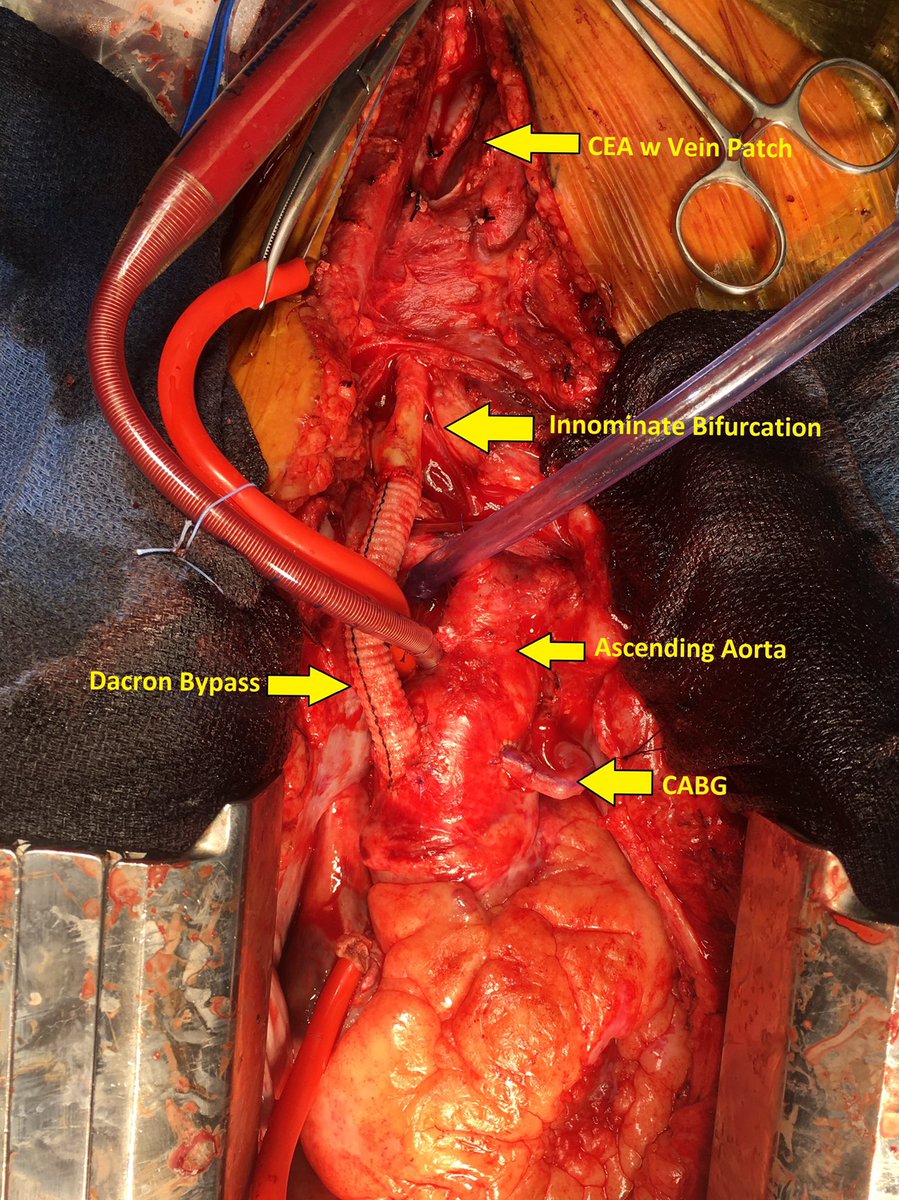

At @UKvascular We encounter a high volume of mesenteric ischemia. In addition to developing our own technique for open bypass & we perform endo revasc as well. Here pgy7 fellow @djbadia and I are performing a retro SMA stent. Good to have a full toolbox #ComprehensiveVascularCare